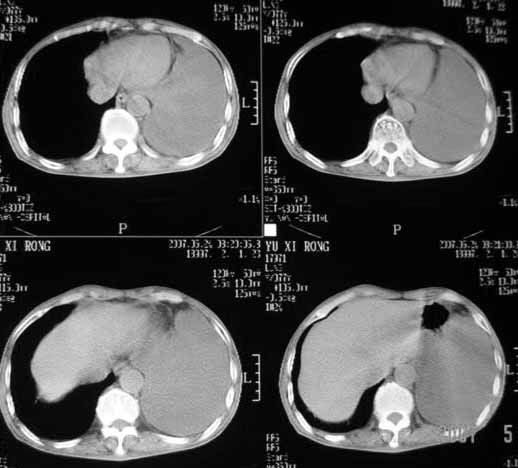

以下是引用luochengyi在2007-5-24 14:33:00的发言:[br]考虑左下肺癌。左侧胸腔积液。

以下是引用adams在2007-5-24 17:12:00的发言:[br]支持“考虑左下肺癌,左侧胸腔积液,建议胸水检查”。[br] [br]

以下是引用fumaogui在2007-5-24 16:20:00的发言:[br]左侧胸腔积液.[br]左下叶不张考虑中心型肺癌[br]建议纤支镜检查.